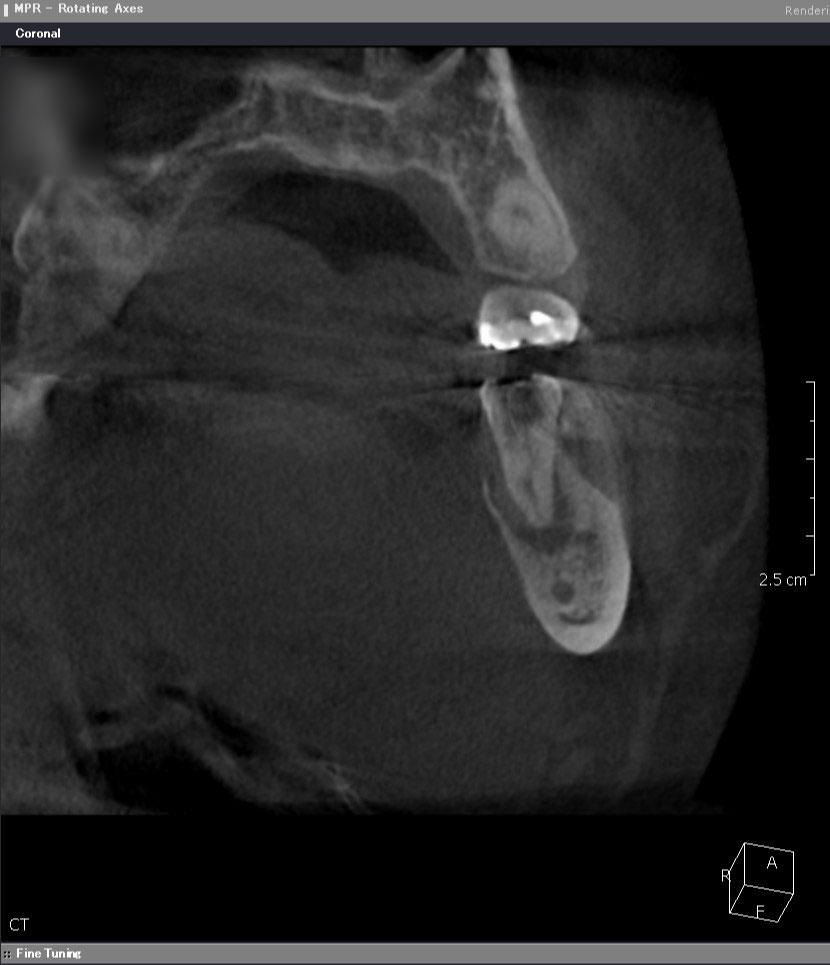

術前CT前頭断

根っこの先の黒い骨透過像(吸収像)をはっきりと認め、特に舌側が著しいです。そのため、舌側の歯茎が腫れてきたと考えられます。一般的には、抜歯と診断されるでしょう。